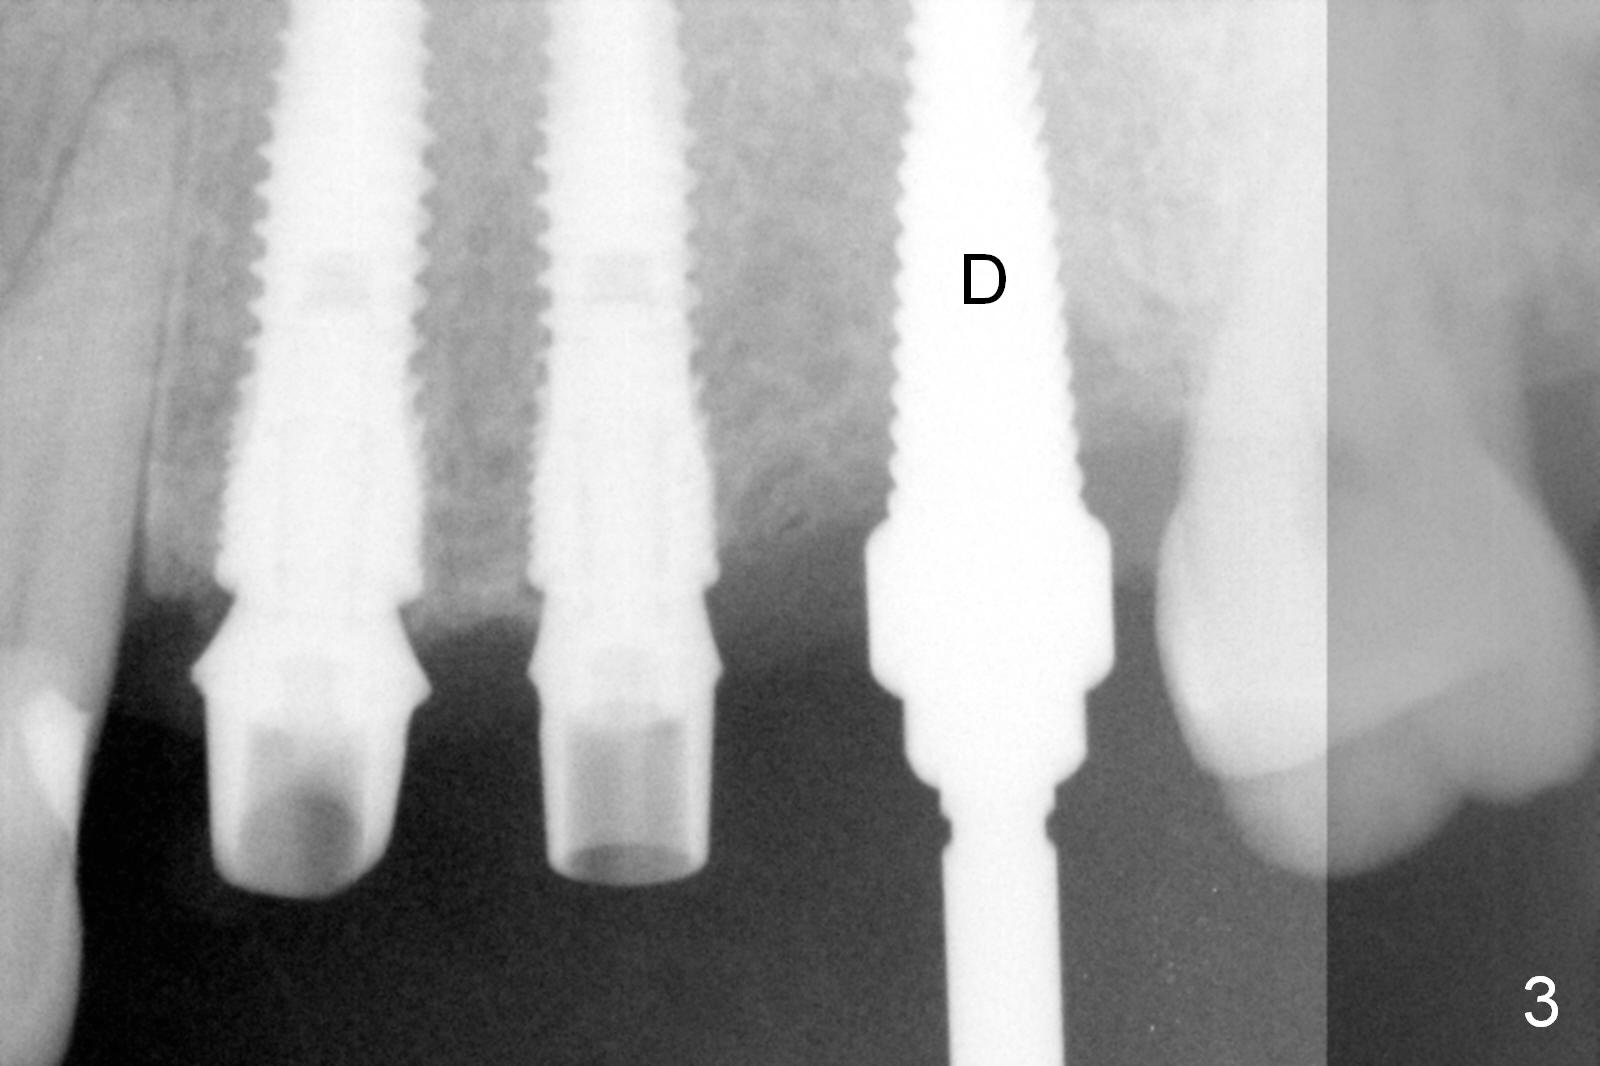

Initial osteotomies are established at the sites of #12-14 through the surgical guide (Fig.1). Following incision, the position of the osteotomies is adjusted buccopalatally where needed. Initial depth is 10 mm (Fig.2); final 14 mm. Ridge split is accomplished between the osteotomies with 7,10 and 13 mm saws from Esset Kit (Hiossen). The osteotomies are enlarged by bone expander drills from the Esset Kit RPM (Fig.3 D). When implants are placed (Fig.4 I (4.1, 3.8 and 5x14 mm)), the gap of split ridge does increase and is subsequently closed by bone graft and membrane. Definitive abutments (A) are installed to hold periodontal dressing in place securely. CBCT study reveals that the bone density between #12-14 are <200 Hounsfield units. When HU is >400, ridge split may result in bone fracture.